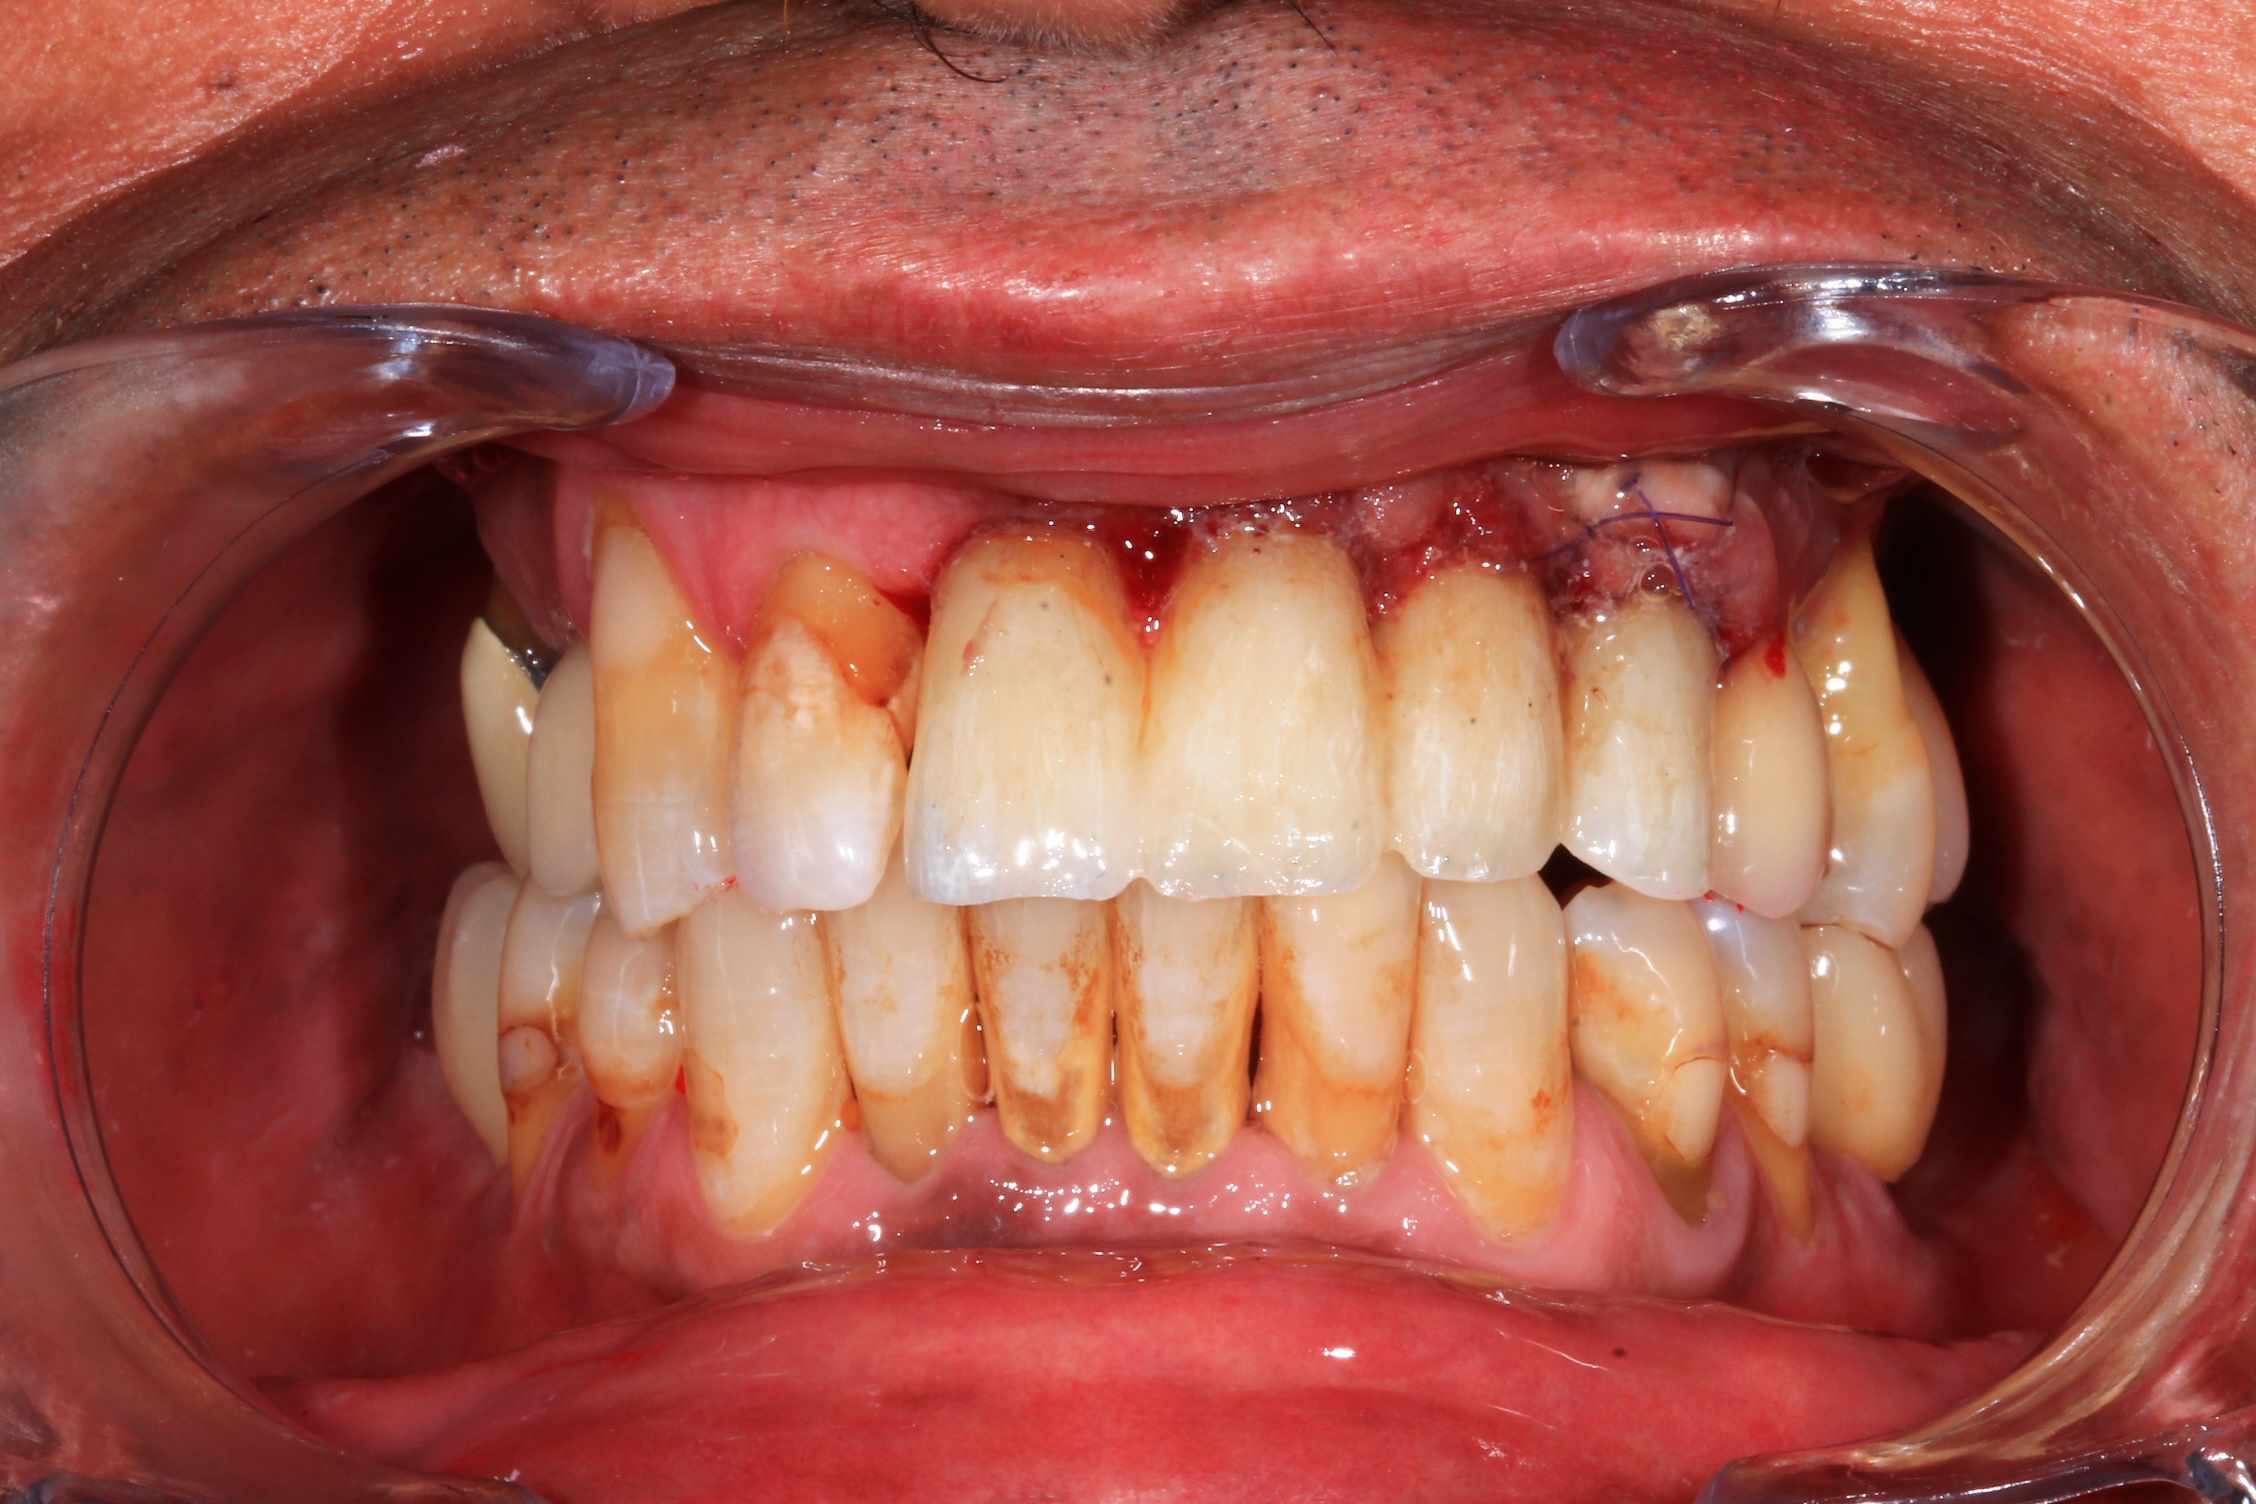

Resultat a une semaine, 3 mois et bridge Full zircone katana maquillé MyIO rosensrew.

1gqmqmfzyv9x6ed0u0o17dmjvrko - Eugenol

F7ppuo81lpm2gsanai908eck3wxu - Eugenol

7cvixvlelz02p2ungdt4jigs85pe - Eugenol

Ub3qcfzgc5qncoqjlls1nx4n6nqo - Eugenol